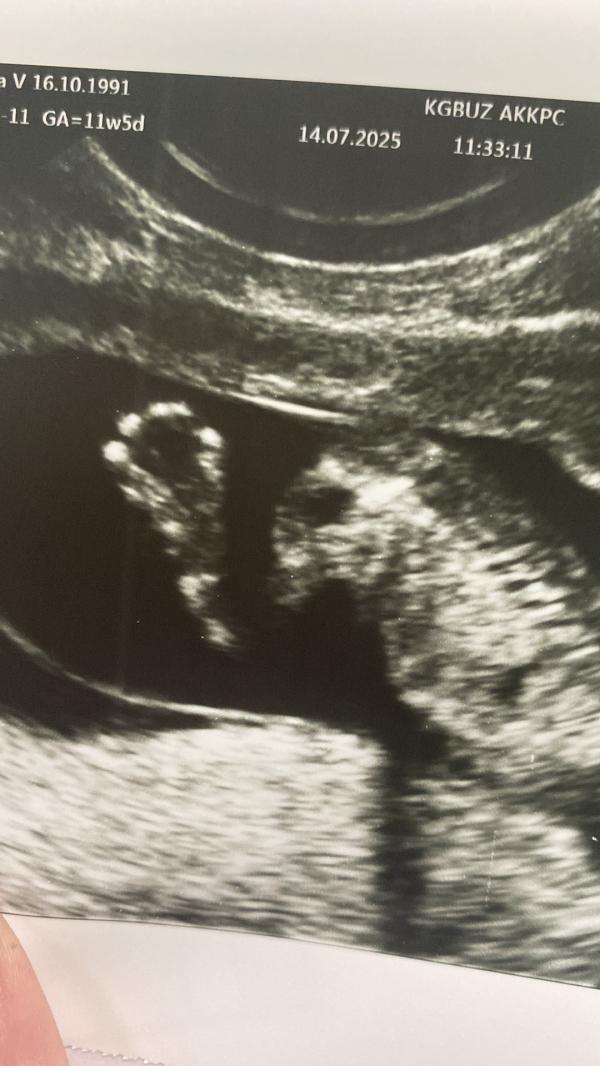

Кстати, был первый скрининг.

Видела пальчики, ручки, для меня было главное, чтобы все хорошо.

После него стало легче дышать, расслабилась.